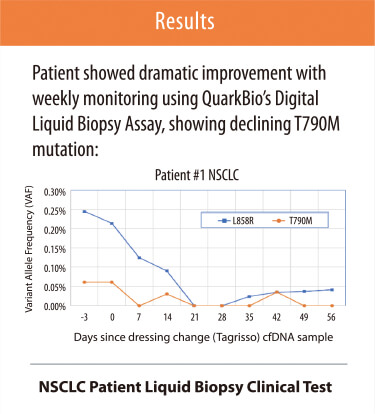

MoDEL™, QuarkBio’s Digital Liquid Biopsy Assay on DigiChip™, detects EGFR T790M drug-resistant mutation in patients with non-small cell lung adenocarcinoma for treatment guidance.

Digital qPCR Applications